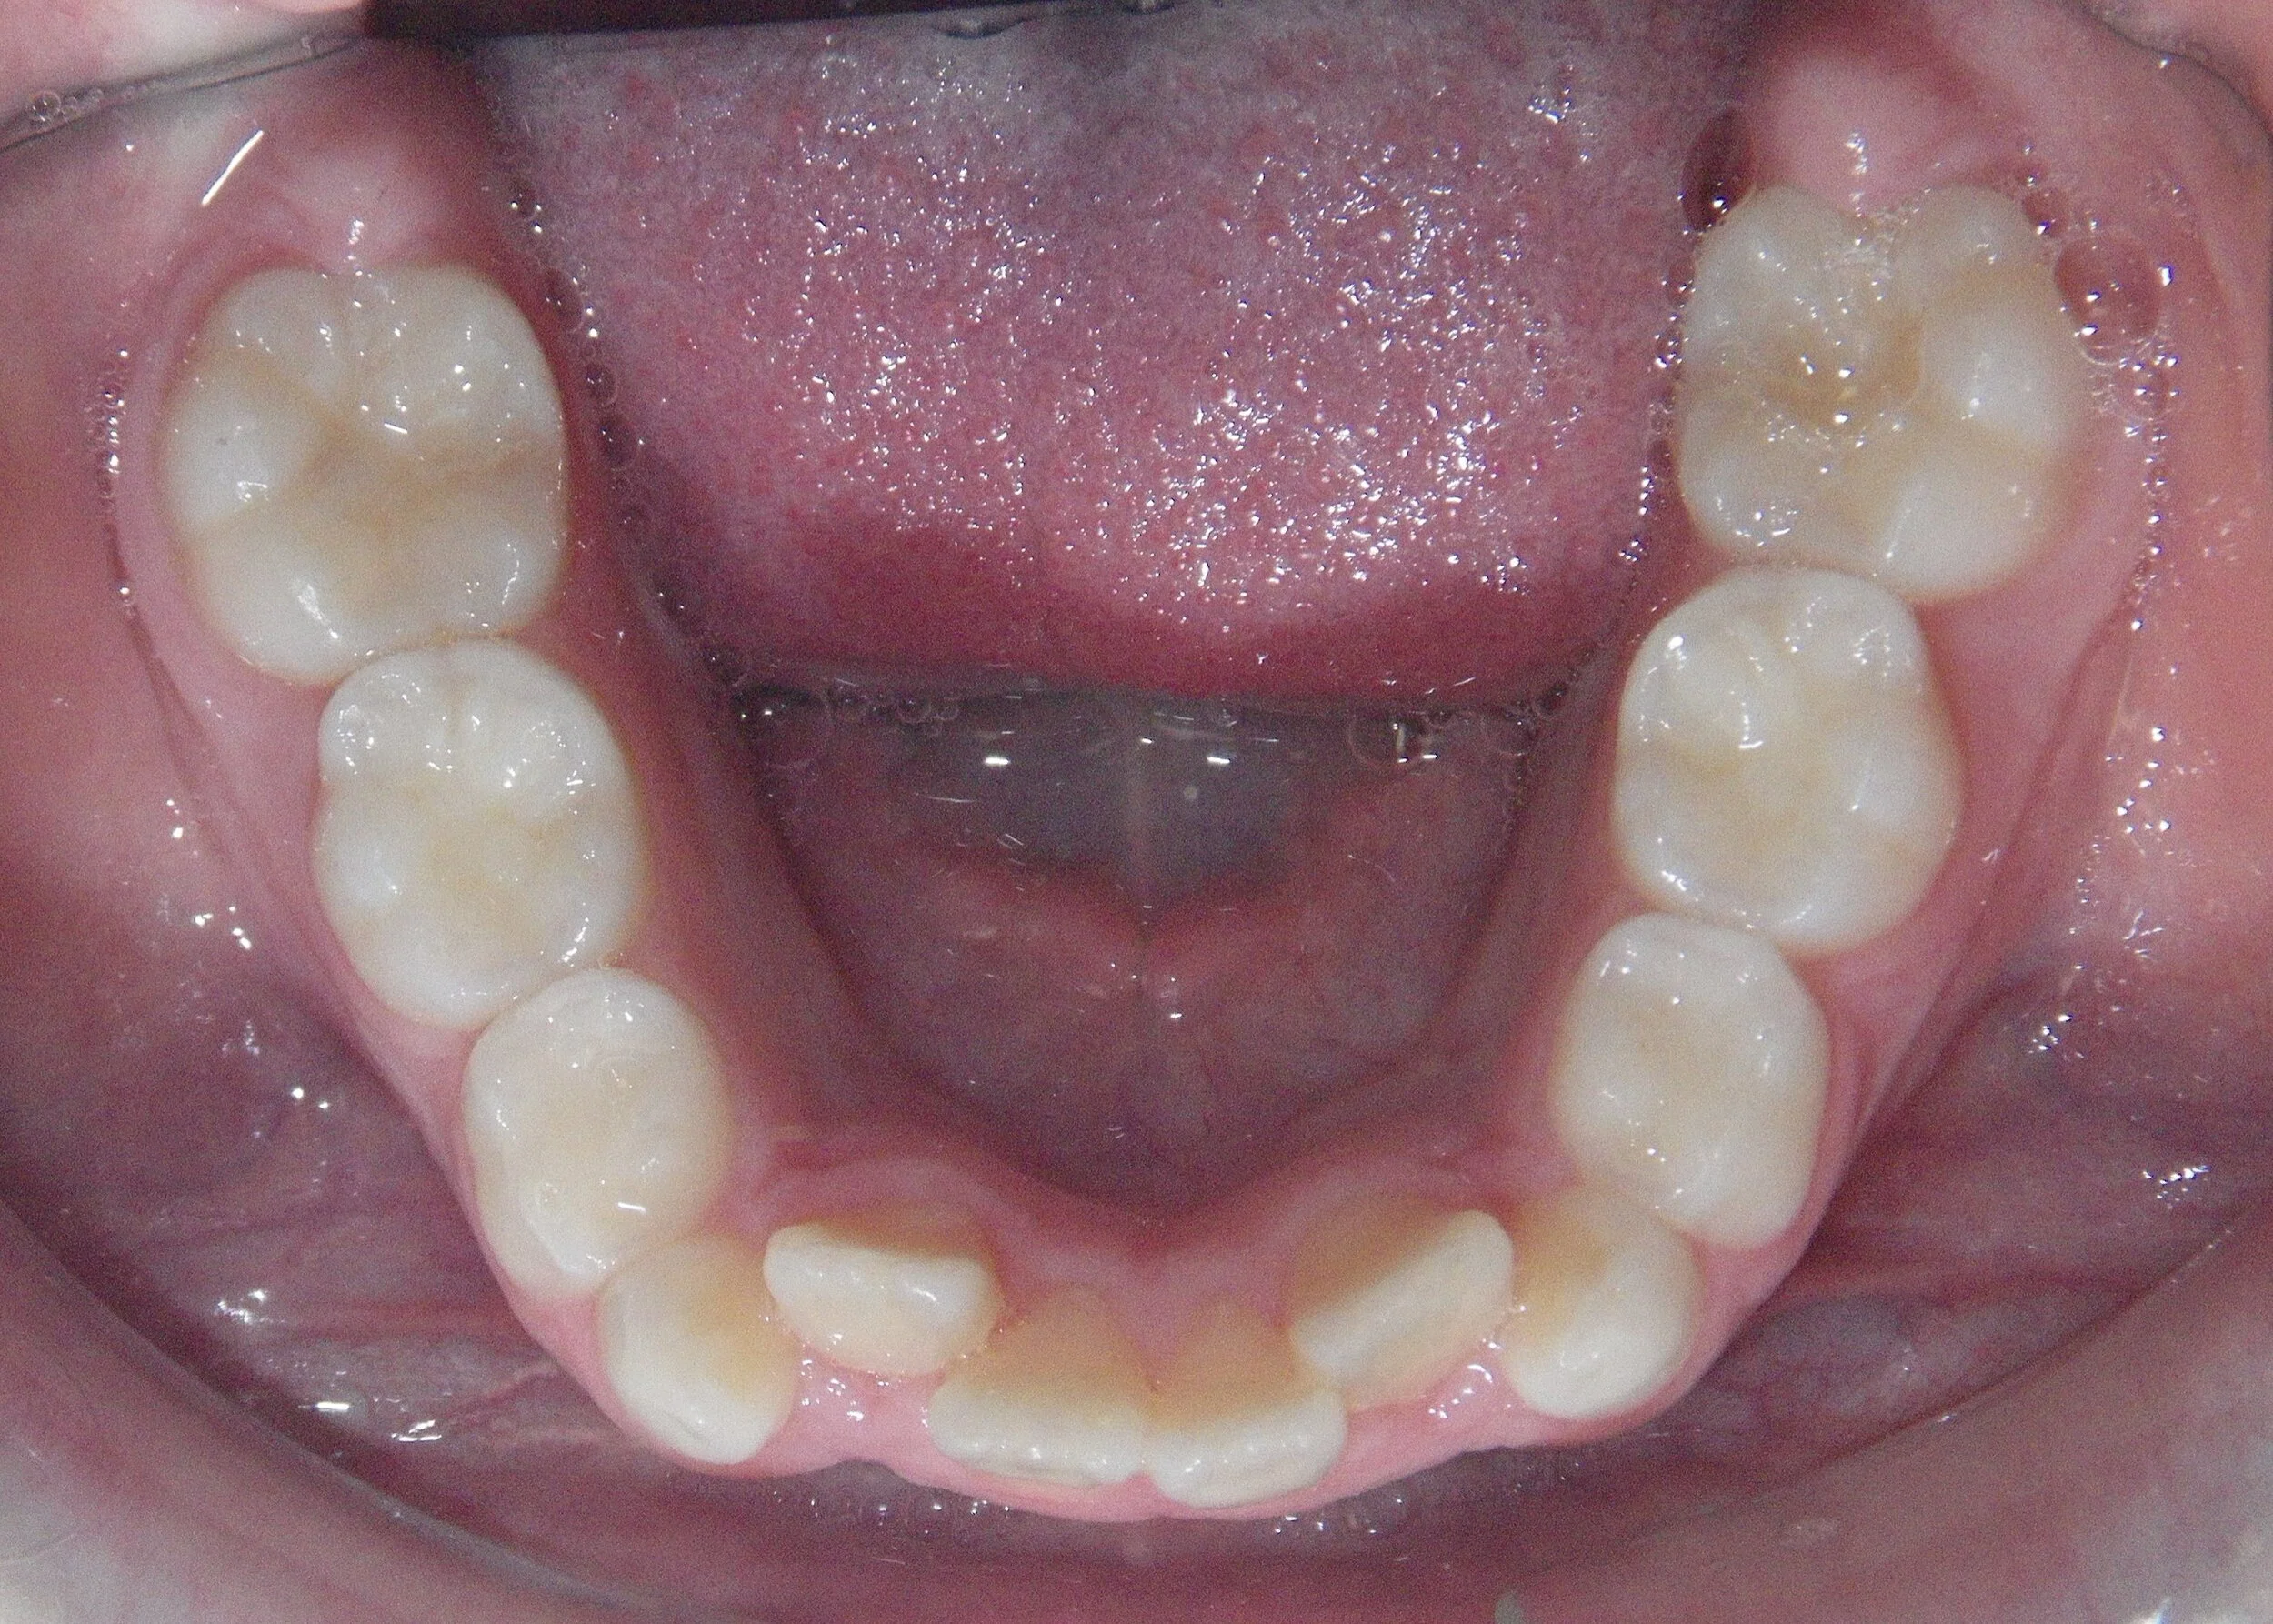

Phase I can be used to help change unfavorable growth or to make room so all the adult teeth have room to erupt. Here, we used Phase I to make room for the adult canines and followed up with Phase II treatment to a get a great esthetic and functional result!